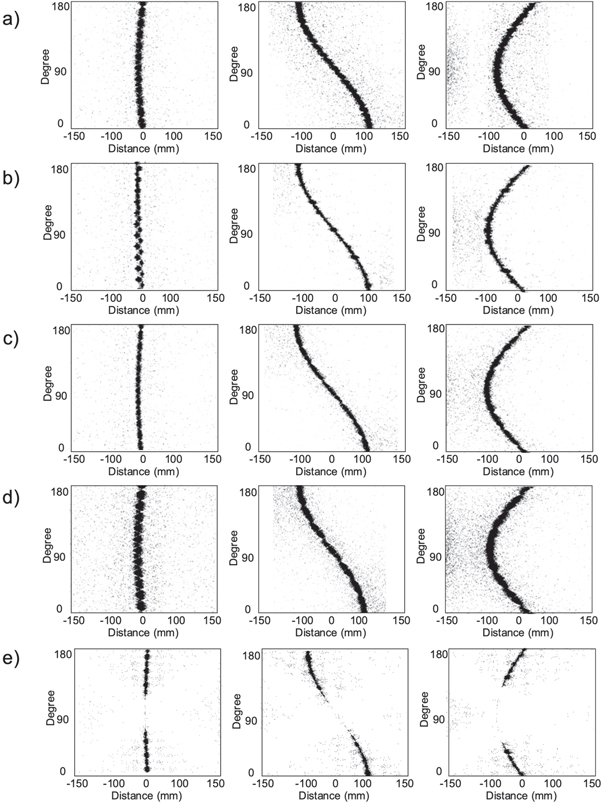

Figure 2 shows the sinograms of three-point sources in the central plane located at 1 mm and 10 mm off center along the Y-axis and 10 mm off center along the X-axis reflecting the simulation of all PET geometrical configurations. The sinograms provide insight regarding the performance of the different configurations.

Figure 2. The simulated sinograms corresponding to the geometry of: (a) the Biograph mCT, (b) large gantry with high-sensitive and high-resolution detector modules, (c) small gantry with high-resolution detectors, (d) small gantry with high-sensitive detectors and (e) partial-ring PET. The first and third columns correspond to a point source with 1 cm and 10 cm offset from the center of the FOV and in the Y-direction. The second column corresponds to a point source with 10 cm offset from the center of the FOV along the X-axis.

Standard image High-resolution imageThe spatial distribution of the underlying signals, intensity, and uniformity of the sinograms are related to the spatial-resolution, sensitivity, and geometrical aspects. The widest and thinnest sinograms are associated with scanners with small bore and high-sensitivity and high-resolution detector modules, respectively. The partial-ring PET illustrates a gap/uniformity in the sinogram corresponding to the lack of detector modules on two sides of the scanner.